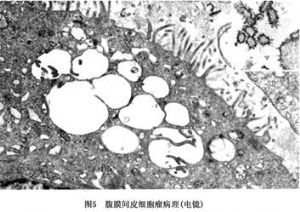

电镜技术特别是透射电镜技术,对诊断间皮肿瘤有极高的价值。其超微结构的特点是:间皮瘤的瘤细胞有众多的、细长的、刷样的微绒毛出现在瘤细胞的表面,但也可出现在细胞质内。但是在腺癌的微绒毛,数量较少,短棒状。间皮瘤的细胞内有巨大的细胞核、突出的核仁,中等量的线粒体被粗面内质网所包绕,常见糖原颗粒,成束的张力原纤维及细胞内空泡。滑面内质网不太发达。细胞外有基板,但多数不太完整。细胞间有连接,也可见桥粒。这些超微结构特点,主要见于上皮细胞性间皮瘤或混合性间皮瘤中。而纤维性间皮瘤,超微结构类似成纤维细胞,在梭形的瘤细胞中,有丰富的粗面内质网,偶见细胞间的微小腔隙以及微绒毛(图5)。

电镜技术特别是透射电镜技术,对诊断间皮肿瘤有极高的价值。其超微结构的特点是:间皮瘤的瘤细胞有众多的、细长的、刷样的微绒毛出现在瘤细胞的表面,但也可出现在细胞质内。但是在腺癌的微绒毛,数量较少,短棒状。间皮瘤的细胞内有巨大的细胞核、突出的核仁,中等量的线粒体被粗面内质网所包绕,常见糖原颗粒,成束的张力原纤维及细胞内空泡。滑面内质网不太发达。细胞外有基板,但多数不太完整。细胞间有连接,也可见桥粒。这些超微结构特点,主要见于上皮细胞性间皮瘤或混合性间皮瘤中。而纤维性间皮瘤,超微结构类似成纤维细胞,在梭形的瘤细胞中,有丰富的粗面内质网,偶见细胞间的微小腔隙以及微绒毛(图5)。